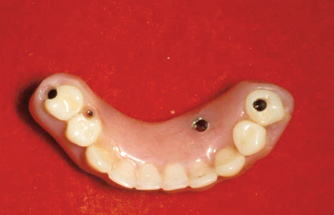

Fig 15. This all-resin interim restoration, which served as a fixed long-term provisional for more than 5 years, is an example of an entry-level option that offers the physiologic benefits of a long-term fixed restoration but with an economic equivalence to a mandibular two-implant overdenture.

Figure 15

Fig 16. This all-resin interim restoration, which served as a fixed long-term provisional for more than 5 years, is an example of an entry-level option that offers the physiologic benefits of a long-term fixed restoration but with an economic equivalence to a mandibular two-implant overdenture.

Figure 16

As an alternative to the relatively expensive traditional hybrid restoration that the senior population may perceive as unattainable at their age, an immediate-load all-resin provisional may often be a reasonable option as an entry-level prosthesis. This can serve for extended periods or indefinitely, and when made with a sufficient volume of resin and opposing a light occlusion such as a maxillary denture, it can offer the benefit of fixed retention at a significant reduction in expense (Figure 15 and Figure 16). Technology involving a guided approach for placing three implants universally in the same sites with pre-manufactured, one-size-fits-all bar components in the mandible can now allow placement of a final restoration in one day, again at a significantly reduced cost (Figure 17 and Figure 18).24-26 Both of these fixed options—the resin long-term provisional and the three-implant bridge—are economically comparable to the most commonly considered implant prosthesis for elderly patients, the two-implant overdenture. In contrast to the latter, however, both fixed restorations offer significant advantages in bite force, bone preservation, maintenance, and patient satisfaction that are simply unachievable with the removable implant overdenture prosthesis.27-31